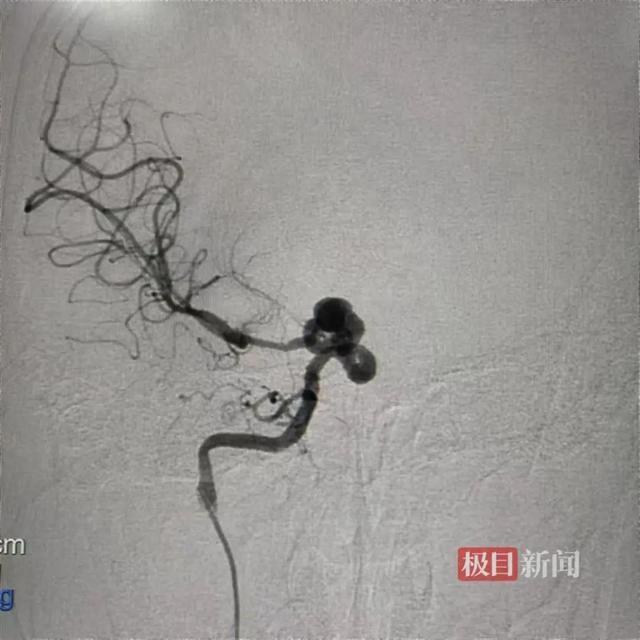

糖糖(化名)颅内的“蛇形动脉瘤”

糖糖(化名)颅内的“蛇形动脉瘤”然而,接诊的神经外科副教授杨海峰发现,糖糖的动脉瘤很少见,且病变处有非常重要的穿支血管,一旦闭塞还会引起偏瘫、昏迷等严重并发症。因此,常规手术都无法安全有效地解决问题。杨海峰教授组织手外科团队讨论,决定采用自体血管移植,在动脉瘤的后段血管上重新建立血液通道,让动脉瘤和病变血管“孤立无援”的治疗方案。通俗地说,就像是河流改道,重新给流经动脉瘤的血流新建一条通道,动脉瘤没有血供之后便毫无威胁,能避免传统手术方式造成的脑梗危险。高难度一站式手术精准“拆弹”1月7日,杨海峰教授团队、手外科陈江海教授团队在手术室和麻醉科的协作配合下,为糖糖实施了“右侧颈外动脉—桡动脉—大脑中动脉”搭桥手术。

杨海峰教授在手术中手术中,两位专家取出糖糖上肢的桡动脉,将其一端与颈外动脉吻合,另一端与颅内的大脑中动脉吻合。然后,夹闭蛇形动脉瘤的近端血管,彻底阻断动脉瘤的正向冲击血流,避免动脉瘤有增大破裂的风险。同时,搭桥的血管可以为大脑提供正常血供,避免夹闭正向血流导致大面积脑梗的发生。据了解,这台复合手术过程很顺利,实现了显微外科和血管内介入手术的无缝转换。最终,造影可见搭桥血管血流通畅,可提供足够的血流代偿,并且穿支血管都得以保留,动脉瘤不显影,手术顺利结束。术后,糖糖的意识逐渐恢复,四肢活动、语言功能恢复正常,没有发生神经功能障碍。“脑动脉瘤多发生于中老年人,发病机制复杂,普遍认为和脑动脉硬化相关。但在青少年中较为少见,像这种‘蛇形动脉瘤’在世界上都非常罕见。”杨海峰教授解释,“蛇形动脉瘤”并非单纯的血管壁一侧隆起“鼓包”,而是病变的一节血管产生严重的扭曲、变形,且随着血流的不断冲击,病变血管逐渐膨大,形成瘤样扩张,一旦破裂危及生命。像这样一节血管的形态都发生了变形,常规手术很可能引起严重并发症,并且无法彻底治愈,病变还会继续进展。杨海峰教授介绍,只有利用自身的健康血管进行移植,进行颅内外血管搭桥,开出的“新路”,既能闭塞病变血管和动脉瘤,也能给大脑提供足够的血流代偿。杨海峰教授表示,脑动脉瘤的发病机制复杂,病变类型多样,要根据患者自身的病变情况制定个体化的治疗方案。来源:极目新闻举报/反馈